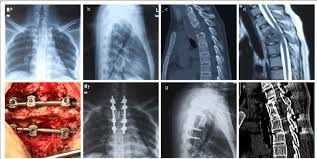

In spite of making rapid strides in healthcare in the last few decades, tuberculosis is still a very common problem in India, Bangladesh, Afghanistan, Pakistan as well as Africa. A bug called Mycobacterium tuberculosis causes TB. Bone TB is the next most common site after lungs. Amongst bones, it is the spine (neck and back) that is the most common site of tuberculosis. Tuberculosis can strike anyone at any age and there may be no specific predisposing factor in most patients. Children and elderly; people with decreased immunity; family history or past history of tuberculosis and patients who have had contact with a known case of tuberculosis are some groups that are prone to developing tuberculosis. Tuberculosis can affect any part of the spine from the upper neck to the tailbone.

Patients with tuberculosis of any part of the spine may complain of pain localized to that area, fever (especially in the evenings), weight loss, loss of appetite and a generalized feeling of being unwell. Their pain may be especially worse at night or during rest. Tuberculosis of the spinal bones can easily spread to the spinal cord resulting in weakness and numbness of extremities, paralysis and alteration of urine and motion pattern. It is this proximity to the spinal cord that makes TB spine a problem that cannot be taken lightly.

The good news is that most cases of spinal tuberculosis can be completely cured just with standard anti tuberculosis medicines. Once a diagnosis of spine tuberculosis is confirmed, your doctor will start you on anti TB treatment (ATT) for 9-12 months. This will typically comprise of 4 drugs – Isoniazid, Rifampicin, Pyrazinamide and Ethambutol. More than 90% patients improve on ATT but a few patients may need Spine Surgery in addition to ATT.